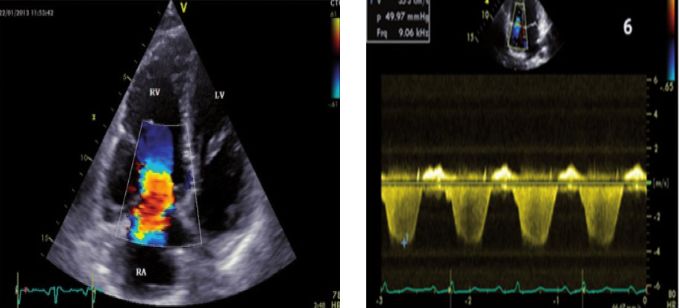

三尖瓣大量返流及三尖瓣反流速度(3.5m/s,压差49mmHg)